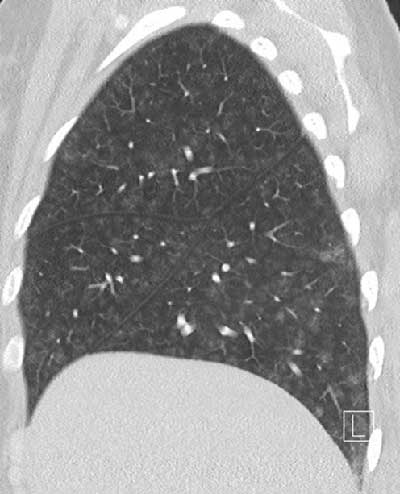

Figure 1

Diffuse groundglass centrilobular nodules without tree-in-bud.

A CT angiogram revealed no evidence of pulmonary embolism. However, diffuse groundglass centrilobular nodules without tree-in-bud pattern were observed (Figure 1), in association with small centrilobular apical emphysema (white arrow Figure 2A) and confluent condensed areas in the basal segments of the lower lobes (black arrow Figure 2B). The first diagnostic hypothesis was hypersensitivity pneumonitis, though there was no air-trapping on the CT. The etiological investigation failed to find any causative agent for this pathology.